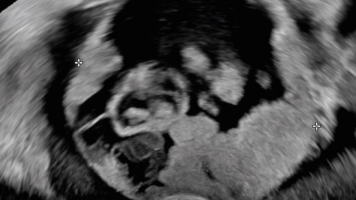

Adenomyose per Ultraschall diagnostizieren

Eine Adenomyose kann mithilfe der Sonographie und unter Berücksichtigung der Anamnese, Symptome und klinischen Befunde theoretisch zuverlässig diagnostiziert werden. Praktisch bleibt es jedoch eine Herausforderung. Anhand charakteristischer Sonographie-Befunde zeigt der Beitrag, worauf Sie achten sollten.